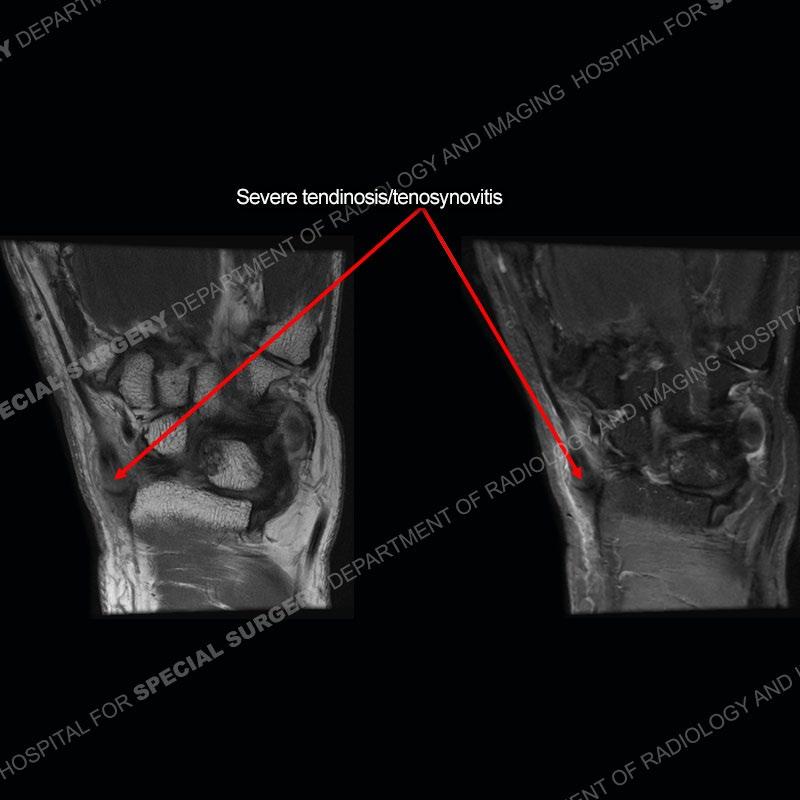

The radiographs in this case are not particularly contributory. The MRI demonstrates tenosynovitis of the first extensor compartment manifest by fluid/synovitis distention of the tendon sheaths. Multiple tendon slips are present of the abductor pollicis longus (APL) and with severe tendinosis seen of one of the tendon slips. Other areas of slightly increased signal and tendinosis are present of the components of the APL. Noted is a somewhat prominent septum separating the more dorsal extensor pollicis brevis (EPB) from the APL.

This case in particular highlights some of the normal variants of the first extensor compartment which can be confusing as well as clinically important. The APL can have multiple tendon slips with the insertion mostly being to the base of the thumb metacarpal but with additional insertions found of the trapezium and occasionally other thenar muscles. With additional tendinosis and partial tearing, this can become particularly confusing.